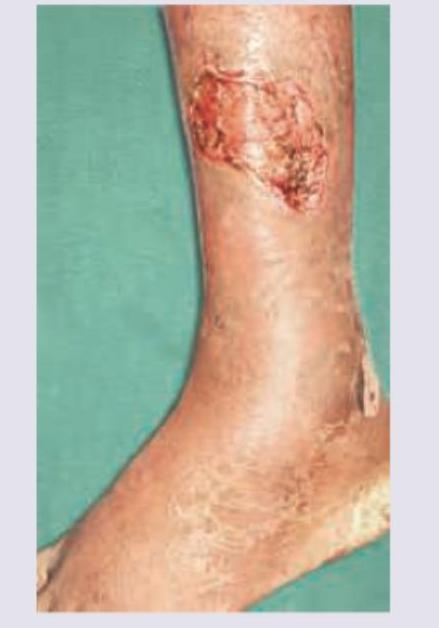

Question 1: A 50-year-old smoker and hypertensive patient presents with the lesion shown below. It is painful and present bilaterally. Peripheral pulses are palpable. What is the diagnosis?

- B. Martorell ulcer (Correct Answer)

Explanation: ***Martorell ulcer***

- This is a **hypertensive ischemic leg ulcer** primarily associated with uncontrolled hypertension, often seen in older patients who smoke.

- Key features include extreme pain, location on the **anterolateral aspect of the lower leg**, and frequently bilateral presentation, despite palpable peripheral pulses.